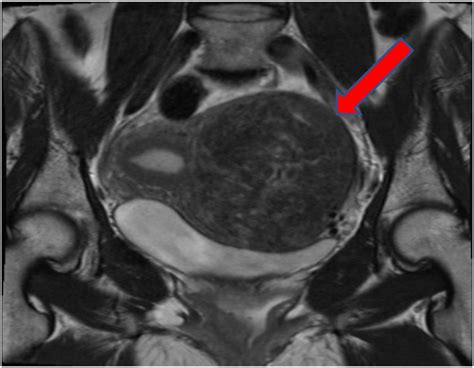

• MRI: Magnetic resonance imaging provides detailed images of the uterus and can help determine the exact size and location of fibroids.